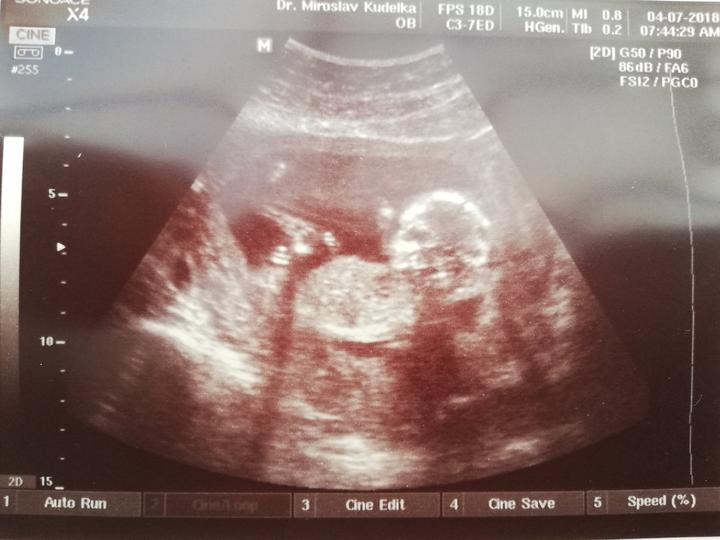

Tak ahoj, dneska jsme absolvovali velky utz a je to HOLČIČKA 😍😍😀 je zdravá a váží cca 450g, zivala a curala 😁😁 úplně živá, od dost vic než jsme takhle viděli našeho prvního😁😊takže máme páreček a přítel měl opět pravdu, že to bude to pohlaví které řekl při pohledu na první těhotenský test. 😍